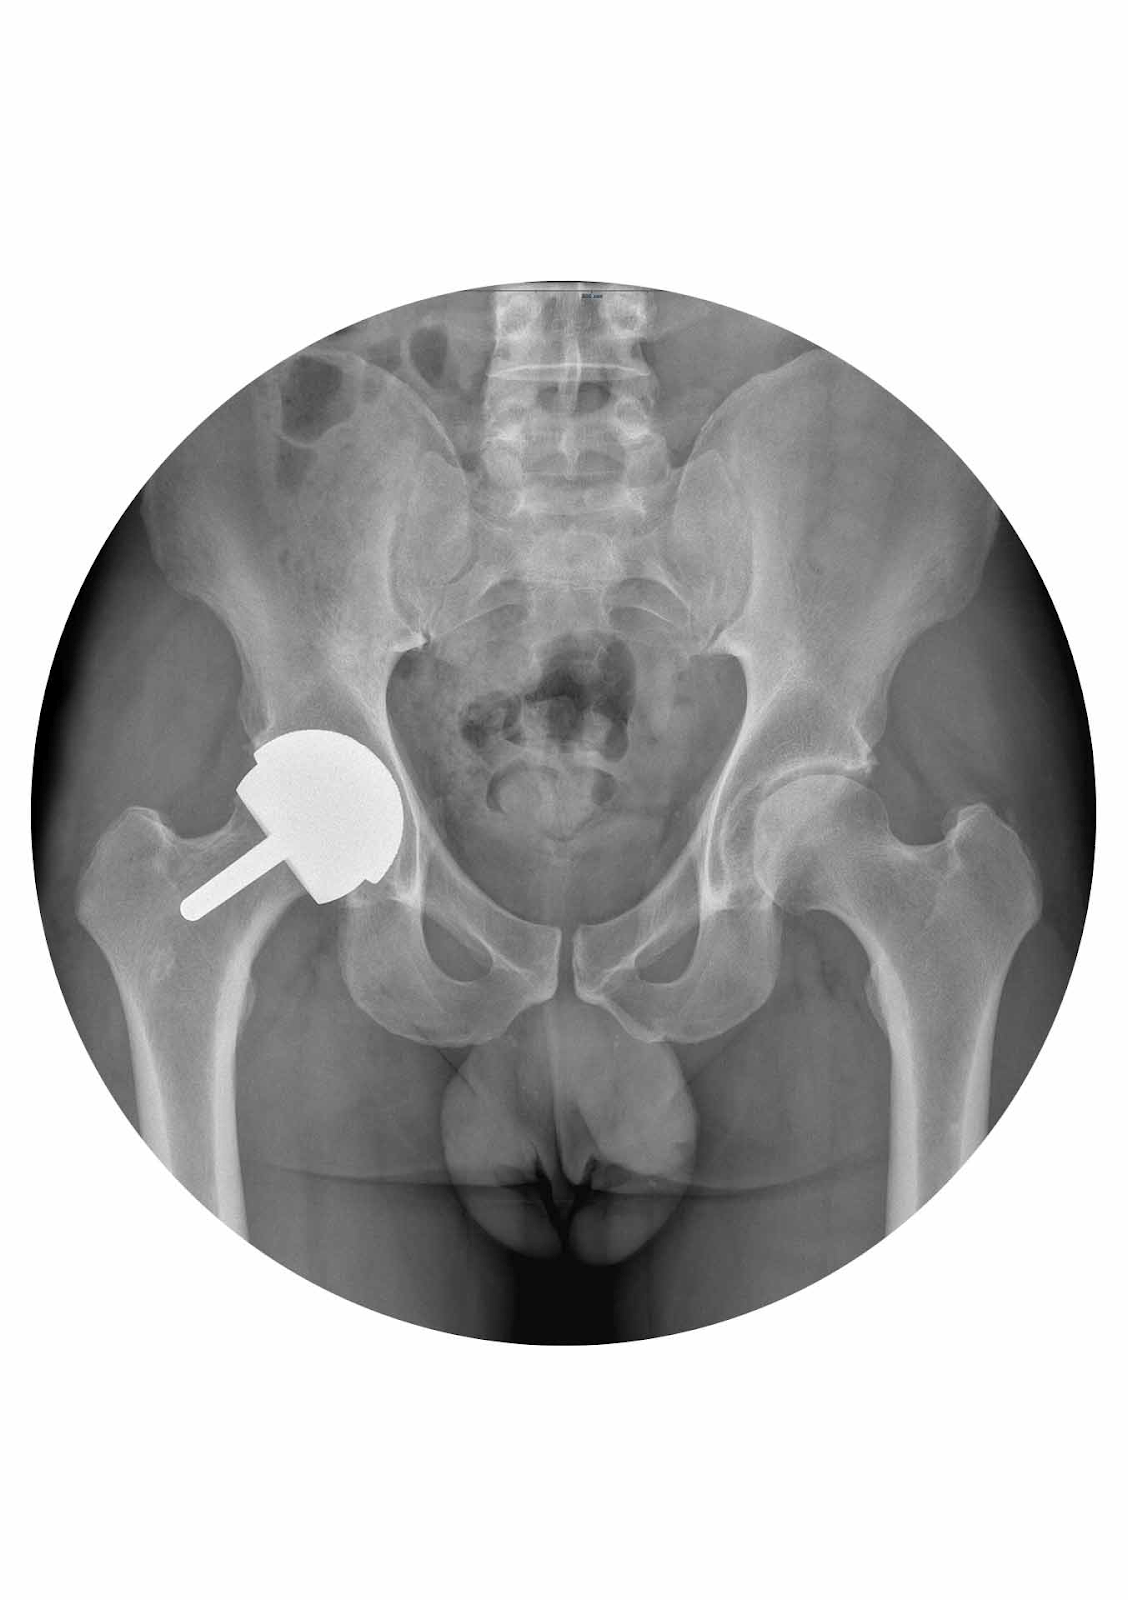

🔹 Artroplastia de tip resurfacing (resurfacing de șold):

- Conservă osul – se „reîmbracă” capul femural și acetabulul cu componente metalice.

- Evită uzura de polietilenă.

- Limitări:

- Contraindicată dacă >1/3 din capul femural este necrozat.

- Risc de fractură de col femural (~1%).

- Controverse privind eliberarea ionilor de metal.

- Nu compromite o eventuală artroplastie totală viitoare.

- Rezultate promițătoare în variantele anatomice focale de resurfacing (ex: la 5 pacienți, 7 șolduri, urmărire >2 ani).